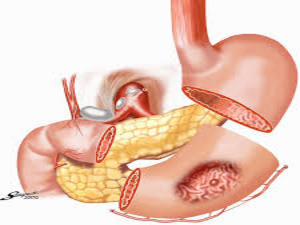

His special interests are in the field of Laparoscopic Hernia Surgery, Laparoscopic Upper G.I Surgery, Laparoscopy in Gastrointestinal Cancers and Bariatric Surgery. He is also actively involved in publications in peer – reviewed journals.